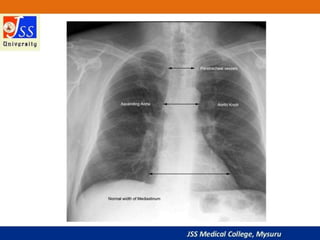

Chest X-rays are commonly used medical imaging tests that produce images of the structures and organs inside the chest such as the heart, lungs, blood vessels, and soft tissues. They can be used to diagnose conditions like pneumonia, lung cancer, and heart failure by detecting abnormalities in these structures. Chest X-rays expose patients to a very small dose of ionizing radiation but provide valuable medical information to guide diagnosis and treatment.